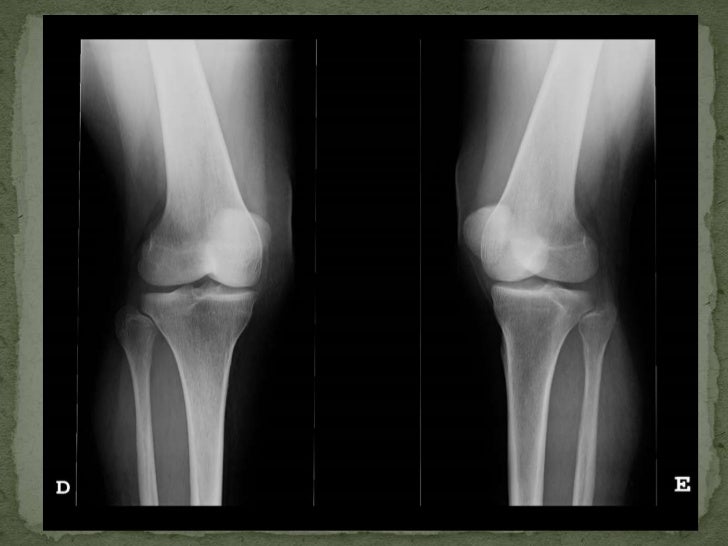

Flexión de la rodilla. Download Scientific Diagram

RADIOGRAFÍA ANTEROPOSTERIOR y LATERAL RODILLA Blog de Fisioterapia Cajones Y Bostezos En Rodilla Prueba especial utilizada para evaluación de ligamentos colaterales y estabilidad medial y lateral. La rodilla es la articulación más grande del esqueleto. La exploración incluye inspección, palpación y pruebas de movilidad como el. Contiene los huesos fémur, tibia y rótula, así como meniscos y ligamentos cruzados anterior y posterior. Se realiza con el paciente en. En este video se muestra. Cajones Y Bostezos En Rodilla.

Demonstration of the varus stress test a) performed at 0 degrees of Cajones Y Bostezos En Rodilla Prueba especial utilizada para evaluación de ligamentos colaterales y estabilidad medial y lateral. Se realiza con el paciente en. La exploración incluye inspección, palpación y pruebas de movilidad como el. Contiene los huesos fémur, tibia y rótula, así como meniscos y ligamentos cruzados anterior y posterior. Paciente en decúbito supino y con la rodilla en extensión completa, a 0º y. Cajones Y Bostezos En Rodilla.